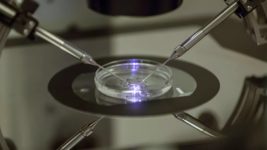

Медики вперше провели штучне запліднення, де майже весь процес виконували роботи та ШІ

Медики вперше провели штучне запліднення, де майже весь процес виконували роботи та ШІ